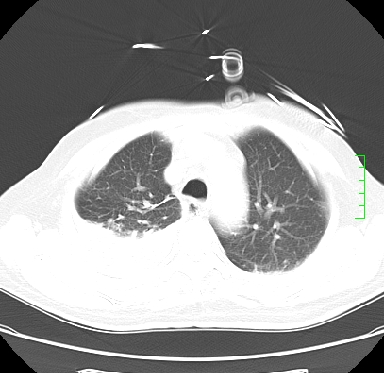

icu病人,几天都没明确诊断。m,76y,咳嗽、咳痰1周,伴气促,右胸痛入院,pe:t38.3c p135 r25 bp135/85。双肺可闻及大量湿罗音,心、腹未见明显异常。诊断:1心衰?2肺部感染?3冠心病?

双肺感染性病变,下叶膨胀不全,胸水,左室大。

1)两肺感染性病变(右肺下叶肺脓肿可能)。2)双侧胸腔积液,以右侧为甚。

混合型肺水肿合并感染,肺膨胀不全,胸膜肥厚粘连包裹,同时肺内有陈旧性病灶。注意复查

ards,肺感染性病变,右下叶实变,双侧胸腔积液,右侧为著,叶间胸膜积液,右上肺陈旧性tb纤维灶,左室大。

考虑双肺感染、右肺下叶肺脓肿伴双侧胸腔积液,肺水肿。

考虑:双肺感染、右肺下叶肺脓肿,双侧胸腔积液,肺水肿.请结合临床.